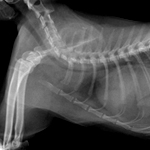

- 방사선 검사

- CR x-ray 사진 장비를 이용하여 흉/복강 내 내부 장기의 모양과 크기 이상 여부, 이물/결석의 진단, 근골격계 이상 여부를 진단하고 있습니다.